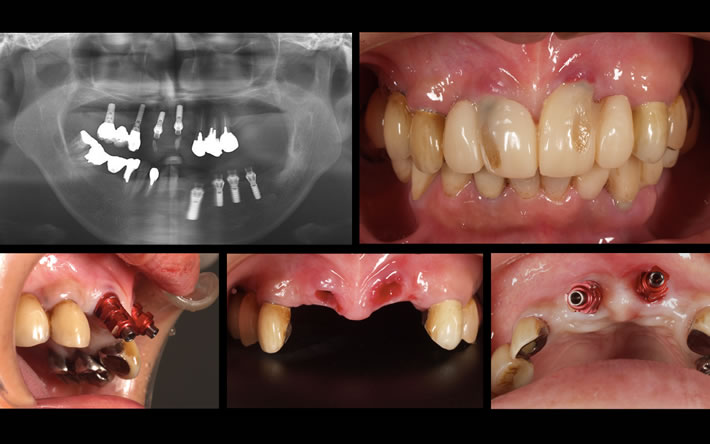

インプラント治療の相場は、30〜40万円です。 1本10万円程度の格安をアピールするインプラントには、十分注意して下さい。 下の写真は、他医院でインプラント周囲炎を起こして転院して来られた方の症例です。インプラントの埋入位置・角度ともに無計画で、それをごまかすために作られた被せ物が、見た目にも極めて不自然です。この状態からリカバリーするには、インプラントを撤去した上で、失った骨を再生をさせるなど、多くの時間と費用がかかってしまいます。

手間を省いた上、粗悪なマテリアルを使うことで、安くすることは可能ですが、 結果的に患者さんを苦しめることになります。 そして、その結果は、数年経って初めて気付く。 長年にわたって真剣にインプラント治療に取り組んできた私達だから分かる この事実を是非ご理解下さい。 ホームページには、いくらでも嘘は書けます。 しかし、症例写真は嘘をつきません。私達は自信があるからこうして多くの 症例を掲載しています。 本当の技術力は、症例を見ていただければ分かります。